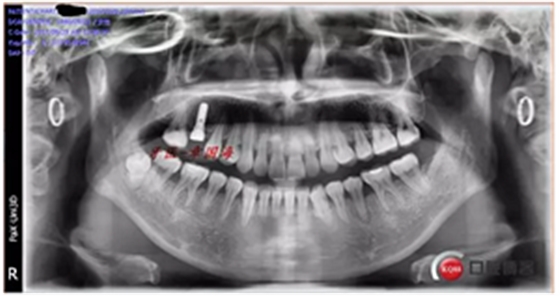

種植后圖片:

附另外一種植前后圖: